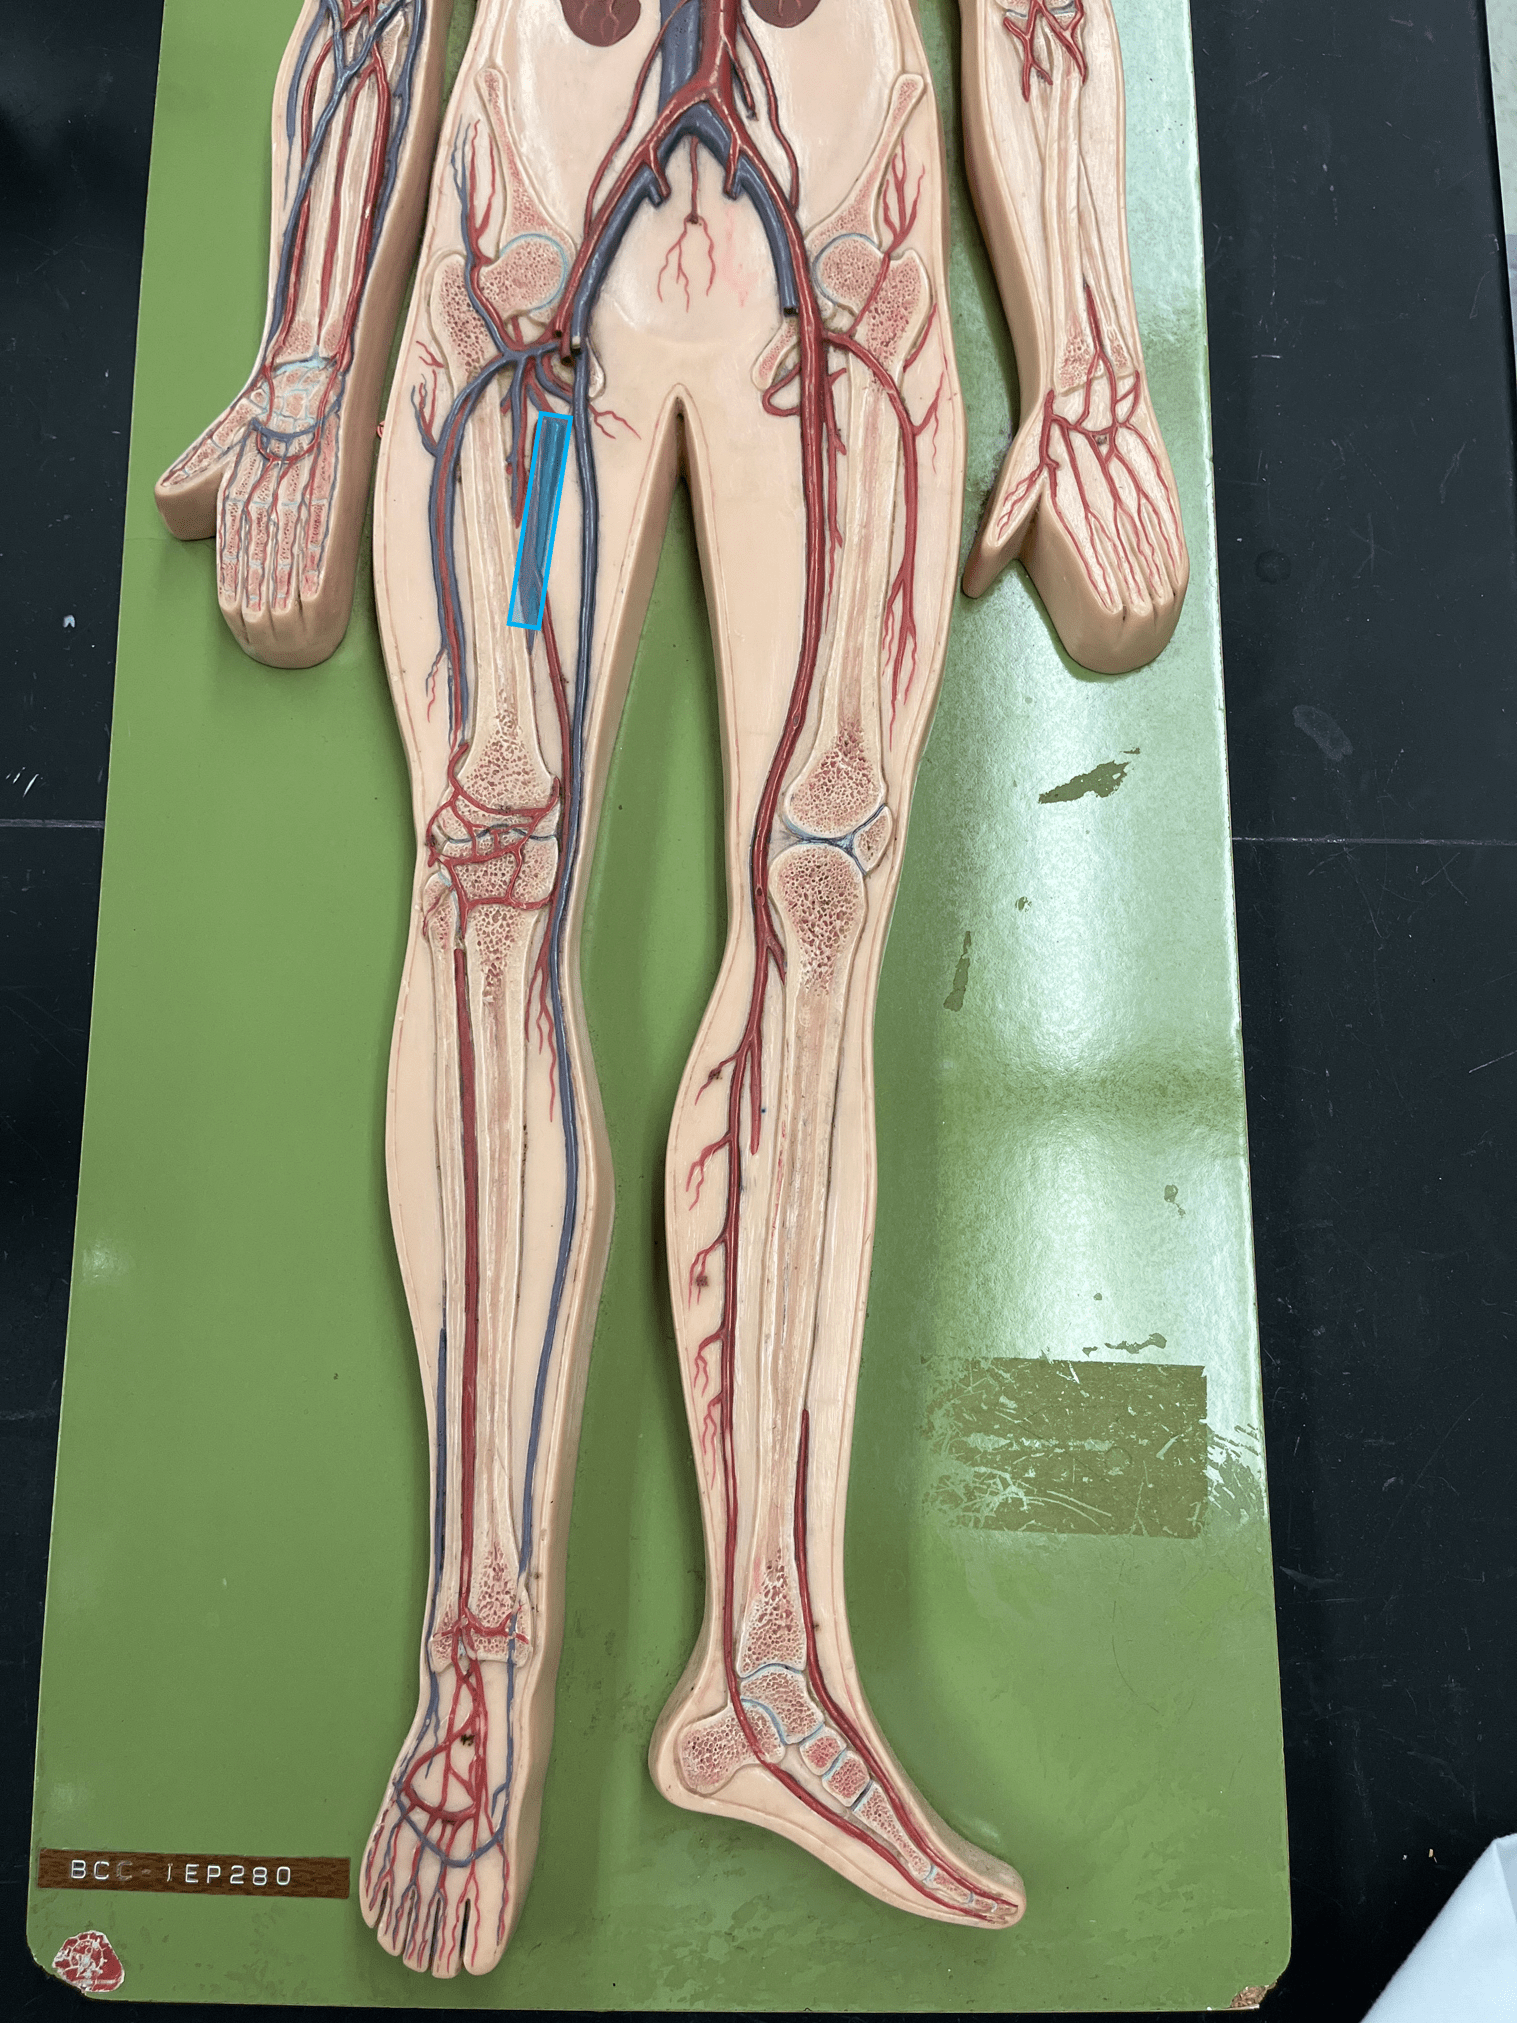

• Part of the tunica interna.

• An artery of the head and neck.

• Originates from the brachiocephalic trunk (R.) or the aortic arch (L.).